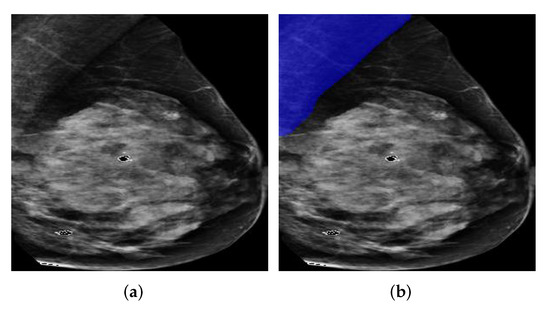

In Figure 9, we show two examples from the two datasets for intuitive interpretation. As can be seen, breast regions only appear in the top left corner while there is a large margin on the right hand size of the images. Therefore, the pre-processing procedure is meaningful to extract breast-only regions from the images and reduces potential overall computational cost. As for the image contrast between pectoral muscle and breast region, the mammography image from OPTIMAM dataset has better contrast as it shows a salient boundary between pectoral muscle and breast while the pixel intensities of the pectoral muscle area and breast area in images from INBreast seem to be more homogeneous.

Figure 9. Mammography image examples from OPTIMAM and INbreast datasets. (a) An example image from OPTIMAM. (b) An example image from INBreast.